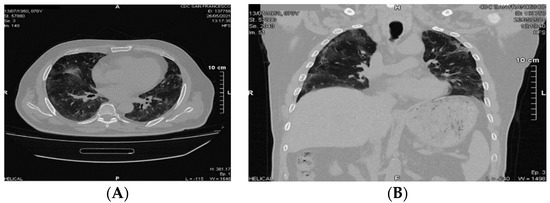

4. Potential Benefits of DOACs in COVID-19

5. Clinical Case